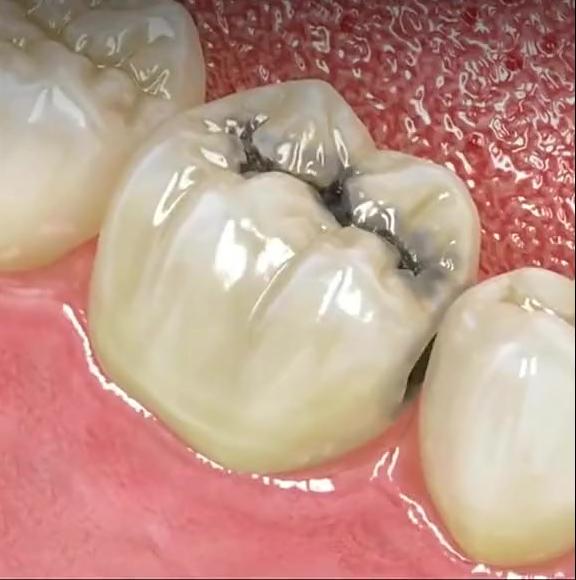

1、出现缺牙间隙

单颗牙缺失时,中间缺失一颗牙,两边的牙齿都会往缺牙的间隙倒,邻牙处出现较大缝隙和移位,最终造成食物嵌塞。